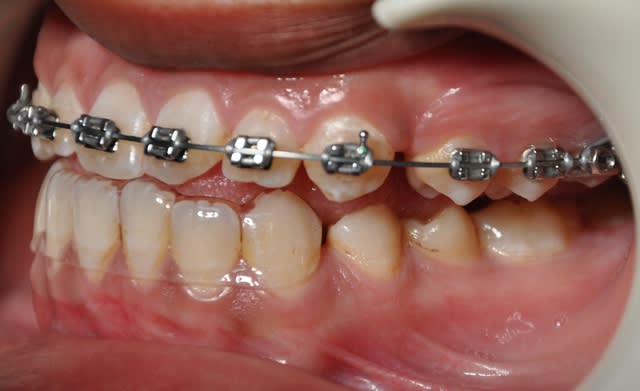

2ème étape

Dsc 0004 lwlouj - Eugenol

Dsc 0003 kobtob - Eugenol

Dsc 0005 pfdneo - Eugenol

Dsc 0006 pndvvp - Eugenol

Dsc 0001 hztqqg - Eugenol

Dsc 0002 b3d098 - Eugenol